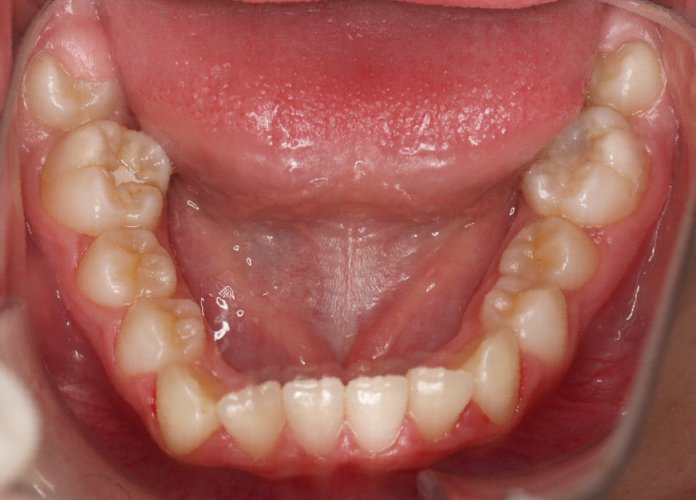

El paciente A.J. de 11 años, acude a nuestra consulta con apiñamiento maxilar importante. El canino lateral (12) está en mordida cruzada. Presenta una Clase II molar y canina, y la línea media está desviada. Se realizó un tratamiento con brackets autoligables metálicos de smartclip 022. La duración del tratamiento fue de 22 meses.

El paciente actualmente ha terminado el tratamiento con brackets y lleva una contención fija de 2-2 en maxilar y 3-3 en mandibular; para complementar también lleva una férula ESSIX durante la noche.

INICIO FINAL